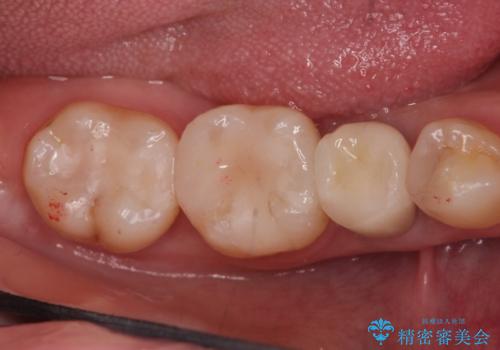

- 他院で前歯の変色をダイレクトボンディングにて修復治療しておりましたが、審美障害を主訴に来院されました。

根管治療後、オールセラミックにて治療を行っております。

ダイレクトボンディングはセラミックに比べ経年劣化しやすい材料です。

今回はオールセラミッククラウンによる治療を行いより審美的な修復ができました。